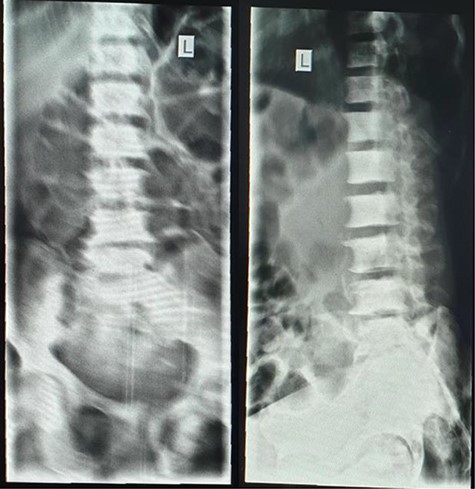

Plain abdominal X-ray (supine) showed grossly dilated large bowels (Fig. 1), and a chest X-ray showed a right-sided pneumothorax, which was managed by a thoracostomy tube (Fig. 2).

A lumbar sacral X-ray relieved severe osteoblastic changes in the vertebral bodies and the pelvic bones (Fig. 4). On chest X-ray, there were the presence of interstitial changes and increased thoracic cage bone density.